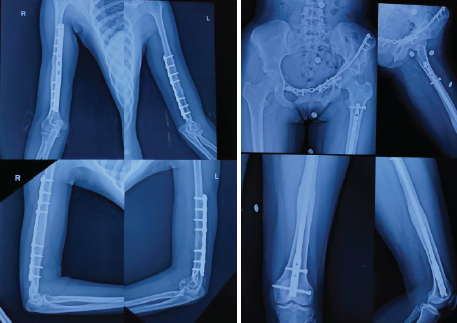

In the second sitting on June 29th, open reduction and pubic symphysis plating was done along with anterior column buttress plating through a modified Stoppa approach to address both the acetabulum and rami fracture simultaneously (Fig. 2c). On July 15th, 2022 the external fixator was removed from the right upper limb; pin sites were healthy. ORIF of humerus fractures were done with 4.5 mm LCDCP through a posterior approach. From the left elbow, K-wires were also removed, and above-elbow support was given for the next 6 weeks. The patient was advised to perform passive and active range of motion exercises in the right elbow and shoulder, and left hip and knee from the 1st post-operative day. The patient was advised to complete non-weight-bearing on the left lower limb for 6 weeks. After 6 weeks, partial weight-bearing was advised with walker support, the slab was removed and left elbow and shoulder range of motion exercises were started. After 3 months, complete weight-bearing was allowed. Active quadriceps, hamstrings, and hip abductors strengthening exercises were also advised. The patient was followed up at regular intervals for a period of 2 years to assess functional and radiological outcomes. After 6 months, the patient was able to do all her daily routine activities. The patient regained her pre-trauma level of activities by the end of 1 year. On the past visit at 2 years, the patient had satisfactory radiological (Fig. 3a and b) and functional outcomes (Fig. 4). Her Harris hip score was 97. The bilateral elbow range of motion was adequate without any instability.

Figure 3: (a) Follow-up X-ray showing bilateral upper arm at 2 years. (b) Follow-up X-ray showing left-sided acetabulum and femur at 2 years.